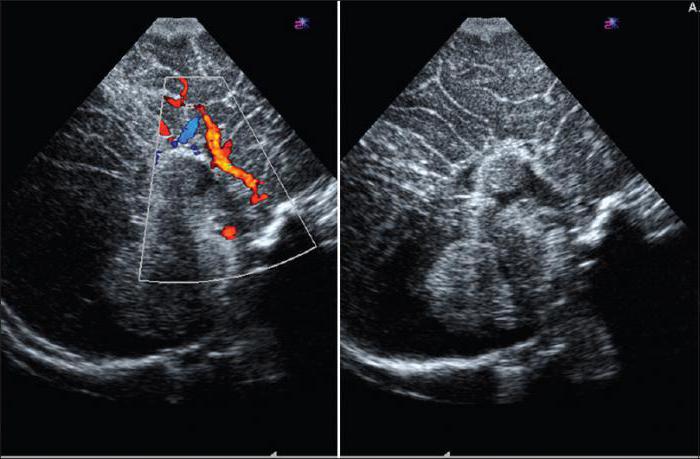

Сочетание ЭхоЭГ с допплерографией позволяет диагностировать такие заболевания, как инсульт и дисциркуляторная энцефалопатия (хроническая ишемия).

Эхоэнцефалография в сочетании с такими методами диагностики, как электроэнцефалография, дуплексное сканирование и ультразвуковая допплерография сосудов головы и шеи, составляет основу диагностики патологий нервной системы.

Сравнительным методом к Эхо ЭГ, но применяемым для исследования сердца, является эхокардиография, или просто эхограмма.

- динамику изменений и причины ухудшения кровообращения в сосудах мозга (при атеросклерозе, вегетососудистой дистонии, ишемии, инсульте и т.д.);